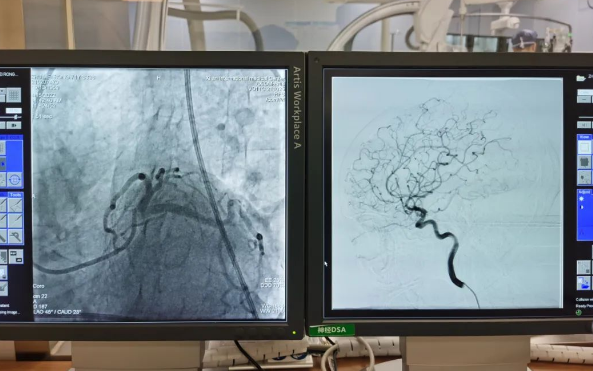

術(shù)前準(zhǔn)備就緒后,心內(nèi)二病區(qū)曾廣偉主任、高釗副主任醫(yī)師、神外科陸丹副主任醫(yī)師共同為患者行腦血管造影術(shù) 冠狀造影術(shù)。術(shù)后,朱奶奶恢復(fù)良好。

陸丹副主任醫(yī)師介紹,由于腦血管疾病和心血管疾病有著共同的病理變化基礎(chǔ)——?jiǎng)用}粥樣硬化,臨床中,兩類疾病交叉存在的情況十分多見(jiàn)?!靶哪X同治”的模式不僅能讓患者獲得較好治療,還能夠降低患者就醫(yī)的時(shí)間成本和經(jīng)濟(jì)成本。